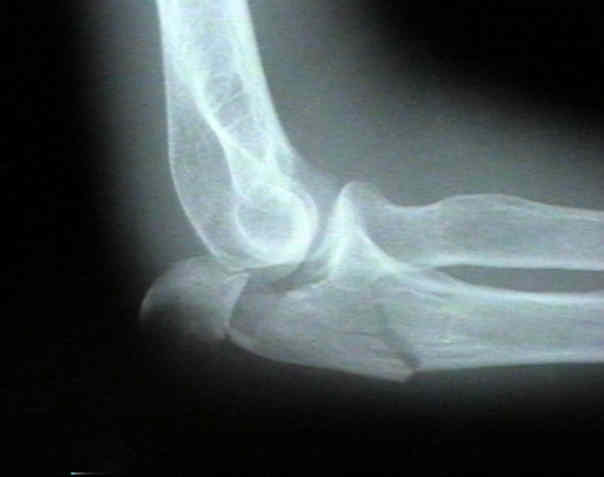

X-elleboog: opnames van elleboog in 2 richtingen (AP en lateraal).